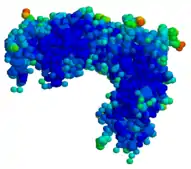

Rasburicase (Q00511) is a tetrameric protein with identical subunits. Each subunit is made up of a single 301 amino acid polypeptide chain with a molecular mass of about 34 kDa. The drug product is a sterile, white to off-white, lyophilized powder intended for intravenous administration following reconstitution with a diluent. Elitek (rasburicase) is supplied in 3 mL and 10 mL colorless, glass vials containing rasburicase at a concentration of 1.5 mg/mL after reconstitution.[3]